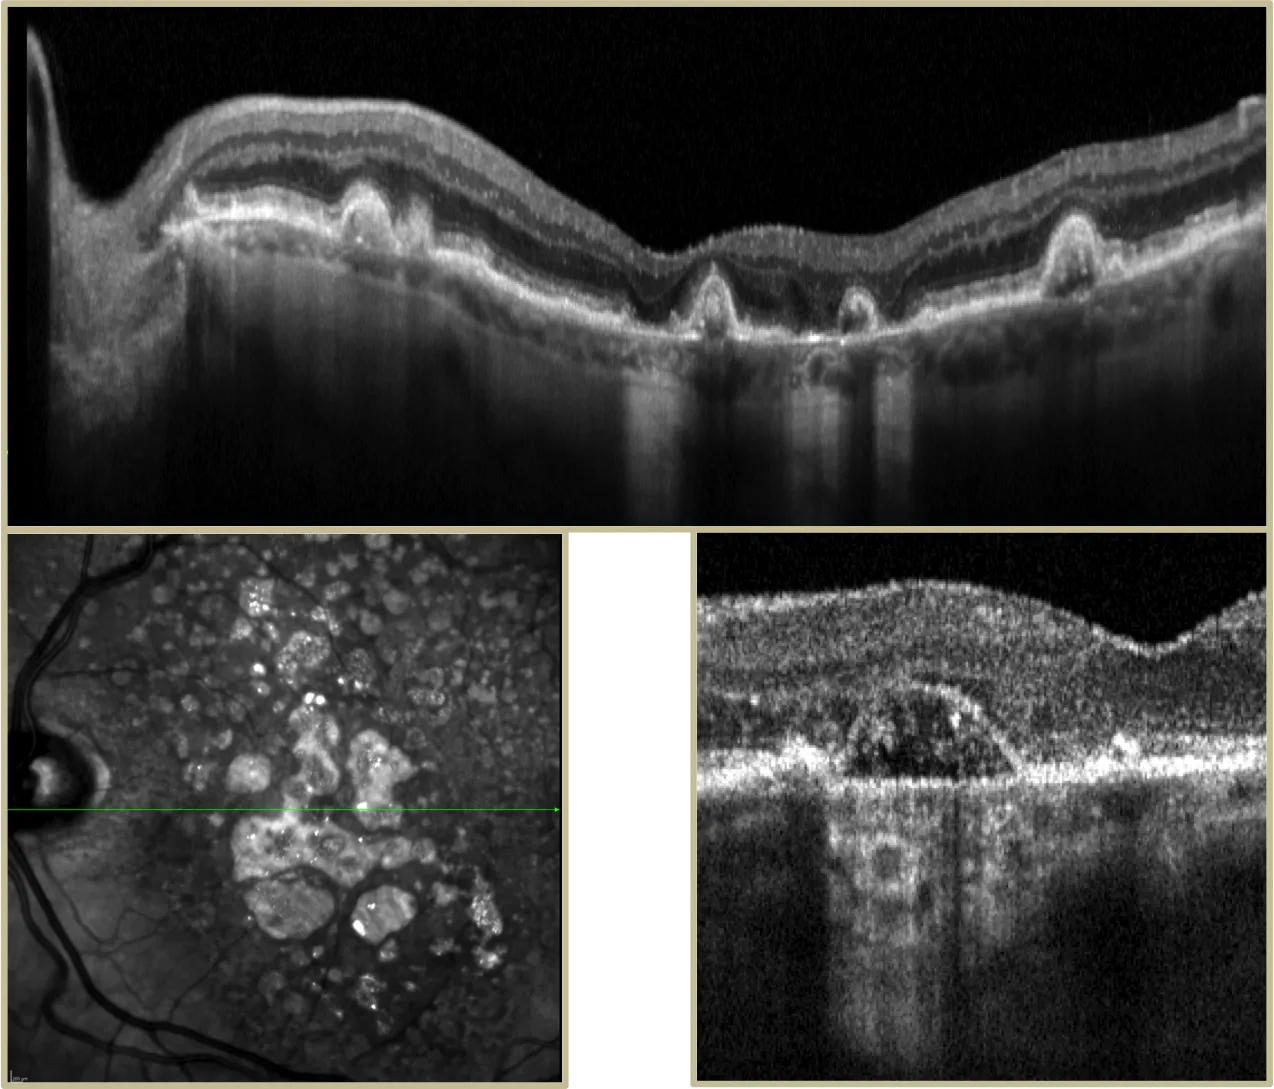

Montage de clichés du Fond d'oeil couleurs montrant quelques dilatations vasculaires visibles en supéro temporal chez un jeune homme de 17 ans dans le cadre d'une maladie de Coats .

Examen d'OCT-Angiographie du même patient permettant d'imager le flux intravasculaire et mettant en évidence de nombreuses dilatations des capillaires intra-rétinien dans la région temporo-fovéolaire dans le cadre d'une maladie de Coats

La maladie de Coats survient majoritairement chez des garçons âgés entre 6 et 8 ans. Les stades précoces de la maladie sont généralement asymptomatiques et l'évolution est variable. De manière générale , les enfants souffrant d'une perte de vision unilatérale ne s'en plaignent pas et le diagnostic est souvent suspecté face à l'aspect anormal du reflet pupillaire qui peut être mieux observé sur des photos ou par recherche du reflet rétinien. D'autres manifestations fréquentes incluent l'apparition d'un strabisme ou un échec lors des examens visuels de routine en milieu scolaire. L'ophtalmoscopie révèle une télangiectasie rétinienne unilatérale et des anévrismes des vaisseaux rétiniens, suivis par des exsudats produisant de dépôts jaunes sous-rétiniens. Les stades les plus avancés de la maladie de Coats incluent un décollement total de la rétine, une leucocorie et un glaucome douloureux à angle fermé.

•Méthode(s) diagnostique(s)

Les explorations diagnostiques incluent l'ophtalmoscopie directe ou indirecte (examen du fond de l’œil en dilation), l'angiographie à la fluorescéine, l'échographie, la tomodensitométrie (OCT) et l'imagerie par résonance magnétique (IRM).